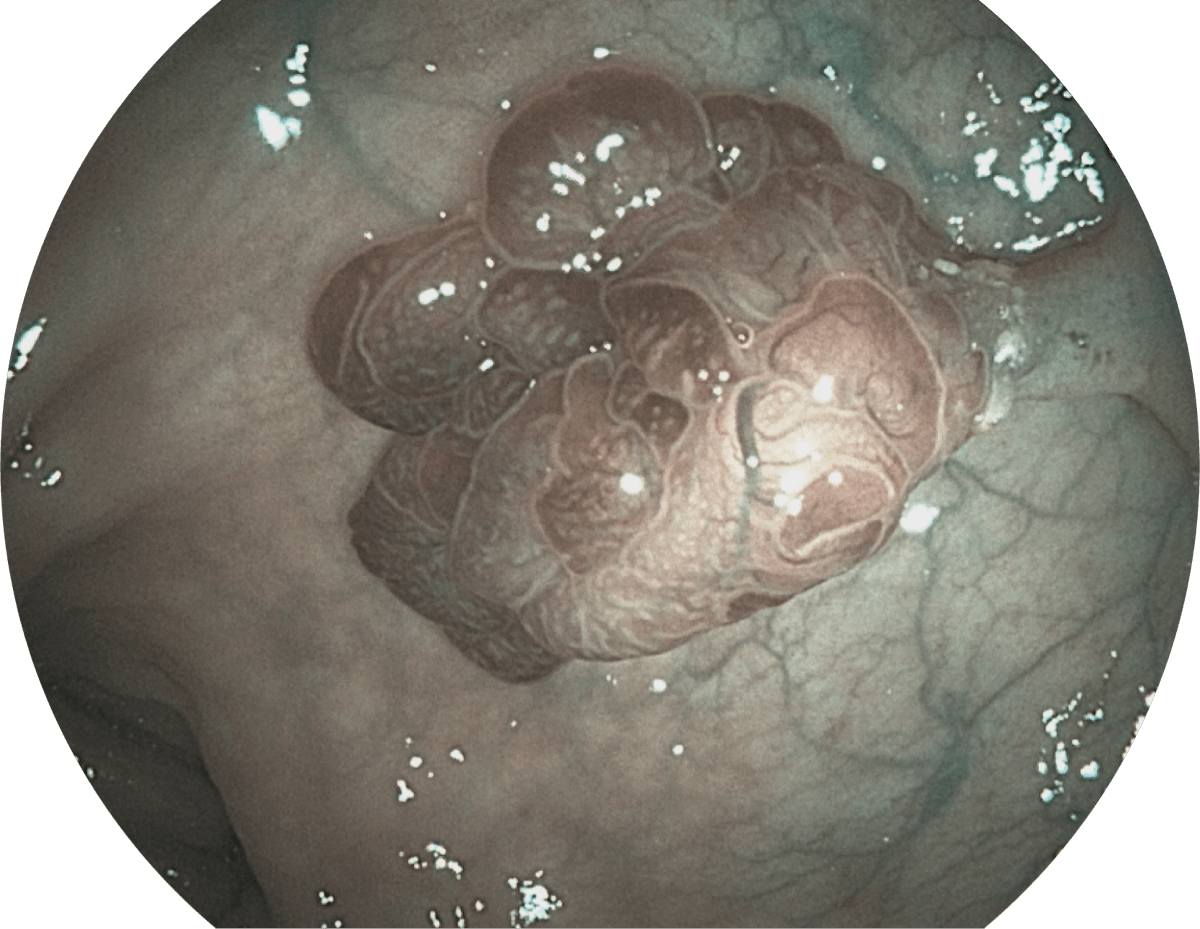

具有聚谱成像技术(SFI)及光电复合染色成像技术(VIST),可完美呈现粘膜细节及病变特征。

(Spectral Focused lmaging, SFI)

SFI